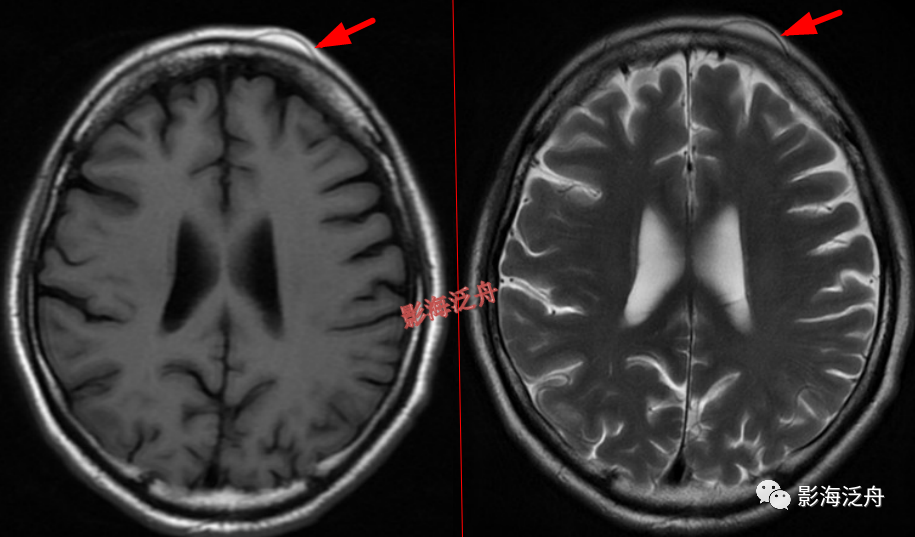

右侧额部头皮下血管瘤。患者为11岁女性,是本病的高发年龄段,这个结节要是漏诊,恐怕会有麻烦。